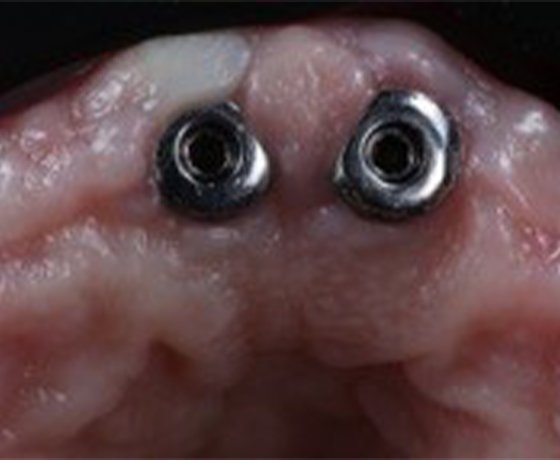

Complex clinical situation with a rare type of implant and discoloration of prepared teeth.